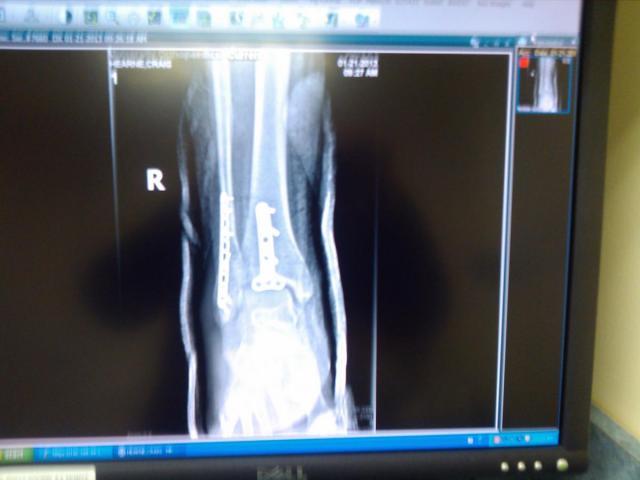

varosd 1,185 #90 Posted January 23, 2013 Craig, Taking cast off and getting into PT is the big benefit of having ORIF(Open reduction,internal fixation). if they just casted a fracture, you have to wait 4-6 weeks in cast then remove and then PT. by putting in plates and screws (better than grade 8) you can start PT and get range of motion and strength back sooner. of course PT will be painful! PT person: Mr AMC Rules, you are gonna hate me, but I'll have you walking soon" :rolleyes: 2 Share this post Link to post Share on other sites

varosd 1,185 #94 Posted January 24, 2013 Craig, looks like you have another problem looks like plantar wart on foot photo? 1 Share this post Link to post Share on other sites

AMC RULES 37,256 #96 Posted January 25, 2013 Craig, looks like you have another problem looks like plantar wart on foot photo? Good eye Don, been there most of my adult life...has never been a problem though. Share this post Link to post Share on other sites